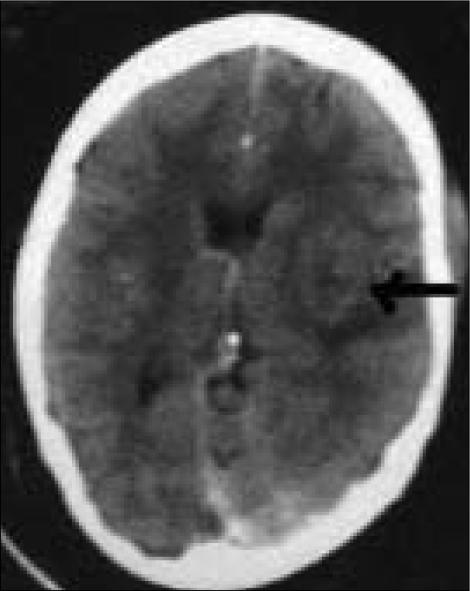

A 25-year-old woman was diagnosed to have tubercular meningitis (TBM) with a right parietal infarct. She responded well to four-drug anti-tubercular treatment (ATT), systemic steroids and pyridoxine. Steroids were tapered off in one and a half months; she was put on two-drug ATT after two months. Six months after initial diagnosis she presented with sudden, bilateral visual loss. Vision was 3/200 with afferent pupillary defect and un-recordable field in the right eye; vision was 20/60 in the left eye, pupillary reaction was sluggish and the field showed a temporal hemianopia. On reintroduction of systemic corticosteroids vision improved (20/120 in right eye and 20/30 in left eye) within three days; the field defects improved sequentially to a left homonymous hemianopia, then a left homonymous inferior quadrantonopia. A diagnosis of TBM, on treatment, with bilateral optic neuritis, and right optic radiation involvement was made. Since the patient had been off ethambutol for four months, the optic neuritis and optic radiation lesion were attributed to a paradoxical reaction to tubercular allergen, corroborated by prompt recovery in response to corticosteroids. This is the first report of optic radiation involvement in a paradoxical reaction in neuro-tuberculosis in a young adult.

一名25岁女性被诊断为结核性脑膜炎(TBM)并伴有右侧顶叶梗死。她对四联抗结核治疗(ATT)、全身使用类固醇和吡哆醇反应良好。类固醇在一个半月内逐渐减量;两个月后她开始接受二联ATT治疗。初次诊断六个月后,她突然出现双侧视力丧失。右眼视力为3/200,伴有传入性瞳孔障碍,视野无法记录;左眼视力为20/60,瞳孔反应迟钝,视野显示颞侧偏盲。重新使用全身皮质类固醇后,视力在三天内得到改善(右眼为20/120,左眼为20/30);视野缺损依次改善为左侧同向性偏盲,然后是左侧同向性下象限盲。诊断为正在接受治疗的TBM伴双侧视神经炎和右侧视辐射受累。由于患者已停用乙胺丁醇四个月,视神经炎和视辐射病变归因于对结核变应原的矛盾反应,对皮质类固醇的迅速反应证实了这一点。这是关于一名年轻成人神经结核矛盾反应中视辐射受累的首例报告。